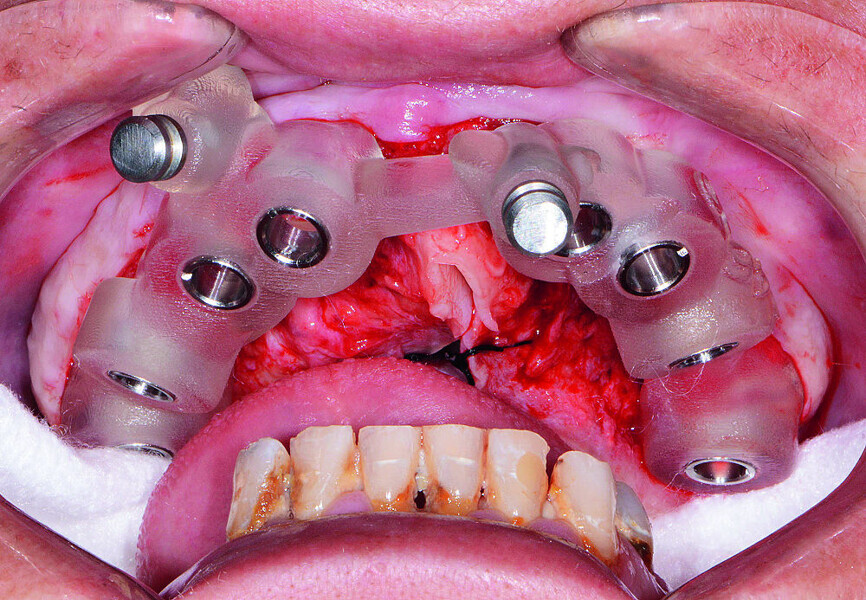

Fig 9 Mise en place du guide chirurgical maxillaire

Fig 10 Tenons parallèles mis en place